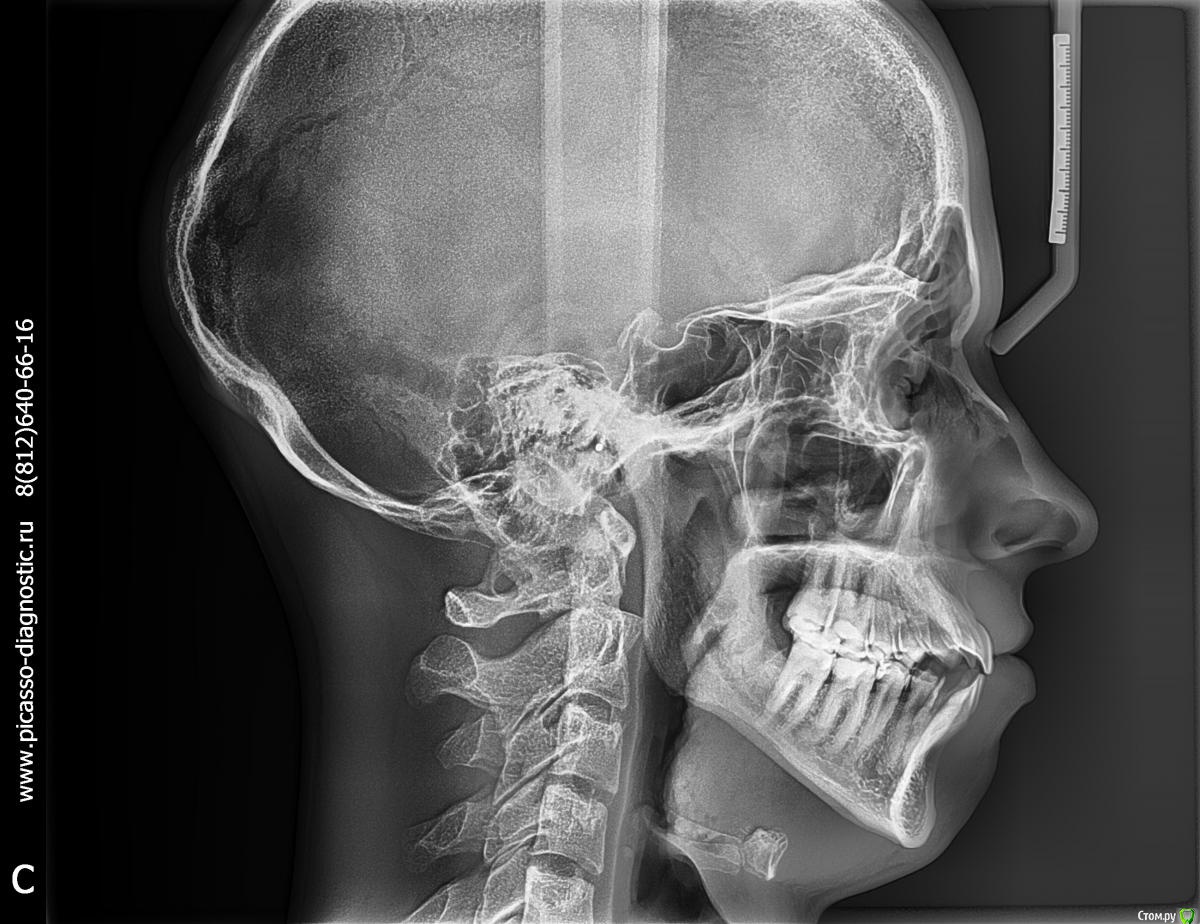

zab Опубликовано 6 октября, 2016 Поделиться Опубликовано 6 октября, 2016 Один врач говорит что так можно брекеты поставить, другой что надо вырывать 4.Спасибо тем кто даст дельный совет. Поделиться своей историей . Ссылка на комментарий

m.d.n Опубликовано 17 октября, 2016 Поделиться Опубликовано 17 октября, 2016 Можно , если вы хотите выровнять зубы и на последствия вам наплевать. Если же хотите и зубы выровнять и красиво выглядеть то и брекеты и операция . и зубы удалять ненадо. НО 1000000 рублей. Ссылка на комментарий

Brigita Опубликовано 26 октября, 2016 Поделиться Опубликовано 26 октября, 2016 (изменено) Я думаю, что скорее всего да- брекеты, подготовка, ортогнатическая операция.А фото покажите? Может и модели есть? Изменено 26 октября, 2016 пользователем Brigita Ссылка на комментарий